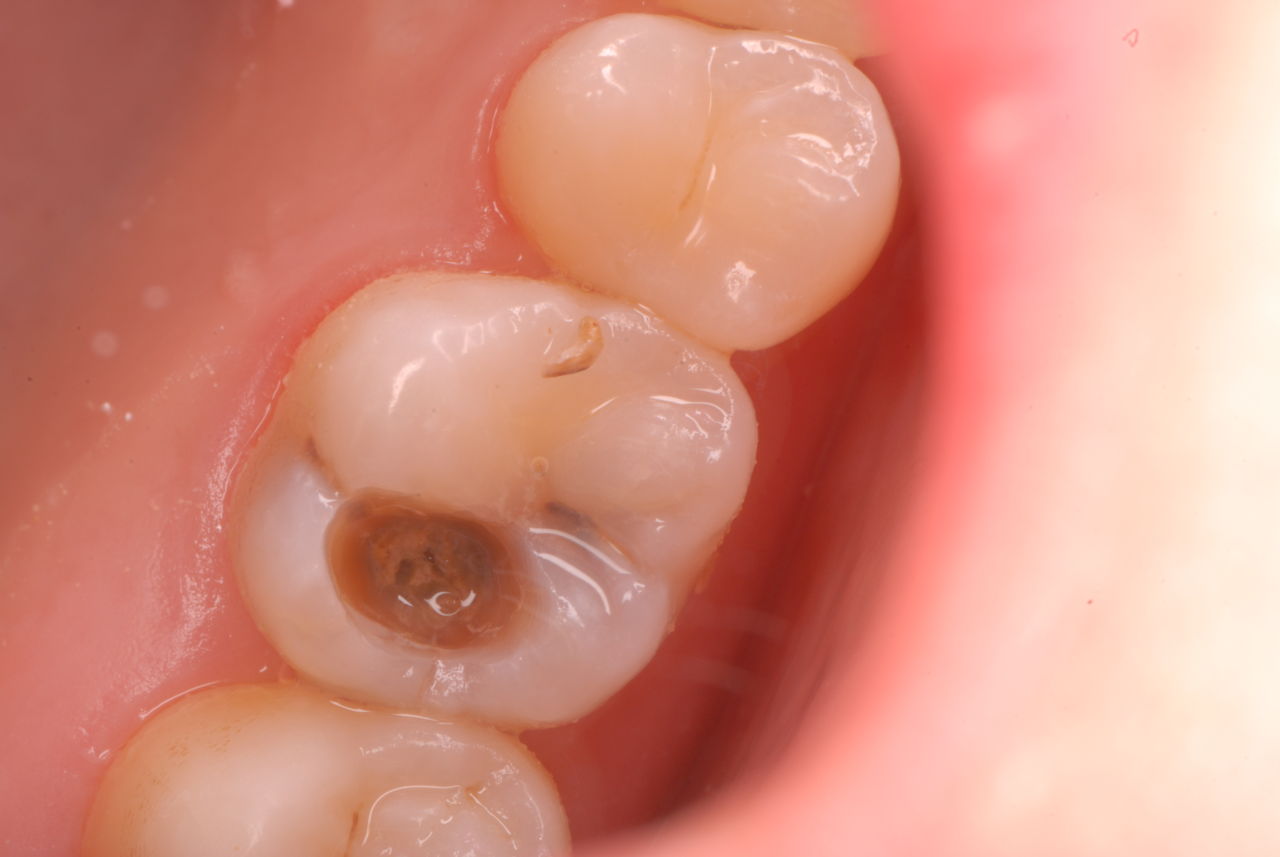

入れ歯の話から入りました。色々不満で注文があるようです。でも話が一段落して口腔内を調べると殆どの歯が重症で抜けそうな歯だらけなのです。

なぜ病気になるのかわからない方が多すぎます。歯が抜けるのは病気だからです。病気を治さずに何かお口の中に入れても土台である歯が抜けてしまっては同じことなのです。